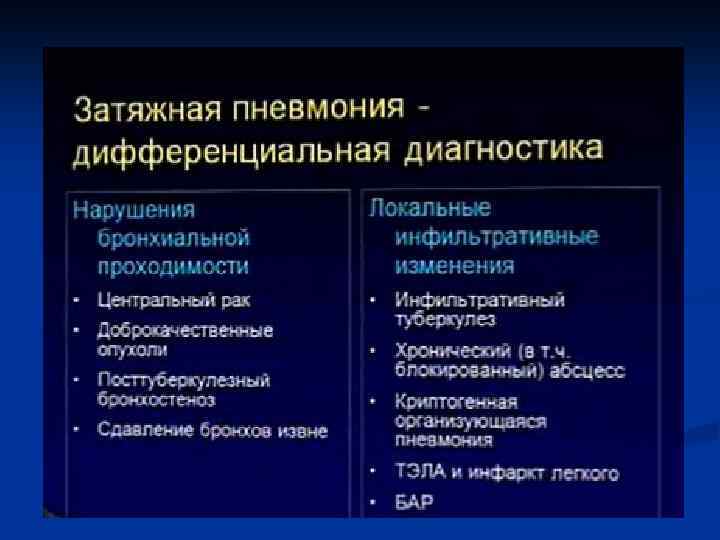

Показания к КТ грудной клетки n n n Недостаточная диагностическая информация стандартного рентгенологического исследования с наличием клиниколабораторных данных при подозрении на пневмонию Стертые клинические и лабораторные данные у больных с подозрением на пневмонию Затянувшийся кашель, субфебрилитет у больных с ОРВЗ Обострения хронических заболеваний бронхо-легочной системы Осложнения в процессе лечения больных пневмонией Затянувшиеся пневмонии